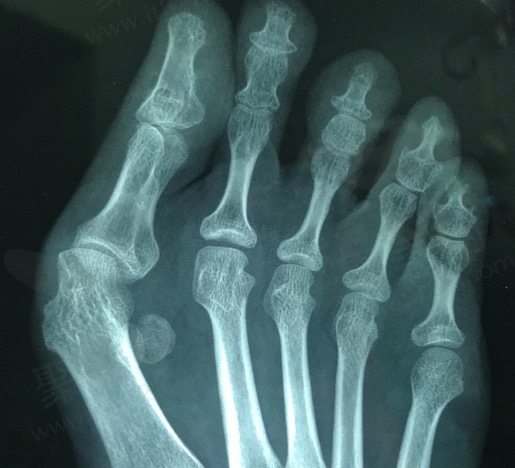

拇外翻是一种常见的足部畸形,表现为大脚趾向外倾斜,甚至与其他脚趾重叠,导致脚部疼痛、关节炎和行走困难。手术是治疗重度拇外翻的有效方式,而李医生的手术技术备受患者认可。

李昕宇医生擅长处理复杂的拇外翻病例,包括中重度畸形和一些由于初次手术失败而需要二次翻修的病例。通过多年的经验积累,李医生开发出了一套有效且个性化的手术方案,能够帮助患者在术后回复正常的足部形态和功能。

李医生在拇外翻手术中采用的是现代化的微创技术。这种技术能够尽量减少对周围软组织和骨骼的损伤,术后回复更快,疼痛感相对较轻。这对患者来说不仅意味着回复期更短,还能尽早回复正常的生活和工作。

在手术过程中,李医生会根据每位患者的具体情况量身定制手术方案。他擅长通过精的骨骼截骨术矫正拇外翻的角度,回复正常的足部力学结构。与此同时,李医生还会考虑到患者的个体差异和生活习惯,确保手术自然、持久。